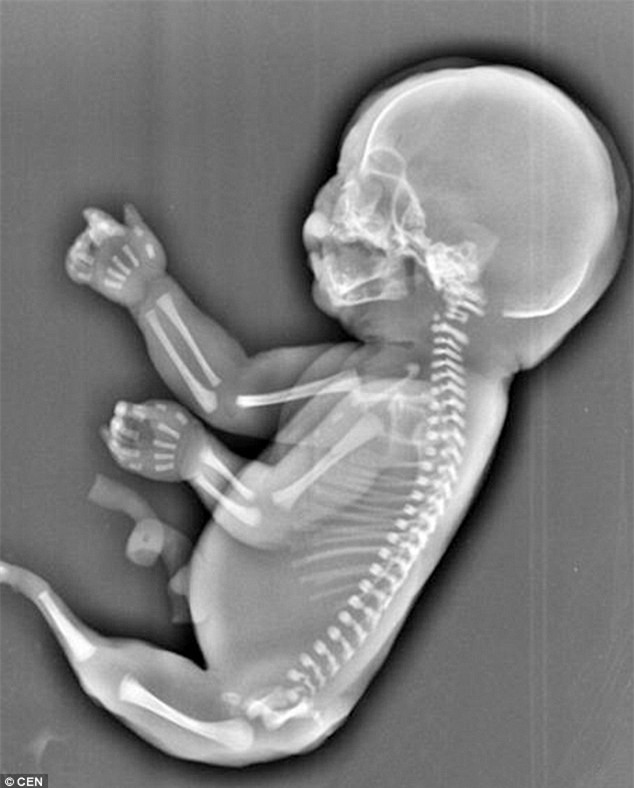

Hình ảnh cho thấy đôi chân em bé bị dính vào nhau như đuôi cá khiến cô Wu phải đưa ra quyết định chấm dứt thai kỳ.

Hội chứng quái ác này khiến thai nhi không có một đôi chân phát triển bình thường mà bị dính vào nhau và mang hình hài tương tự đuôi cá.

Theo tờ Daily Mirror, sau khi cô Wu siêu âm, các bác sỹ cho biết thai nhi có "đuôi cá". Bé còn gặp các vấn đề về phổi và không có bàng quang. Các bác sĩ kết luận rằng thai nhi bị mắc một chứng bệnh dị dạng gọi là Hội chứng người cá (Mermaid's Syndrome).

Theo các báo cáo, hội chứng người cá là trường hợp dị dạng bẩm sinh cực hiếm gặp khiến thai nhi có hai chân bị dính liền với nhau giống như đuôi cá và khiến các bé sinh ra giống như người cá. Trường hợp này chỉ xảy ra với tỉ lệ 1/100.000 và thường thì các bé chỉ sống được từ một vài giờ đến vài ngày do biến chứng liên quan đến sự phát triển và chức năng của thận.